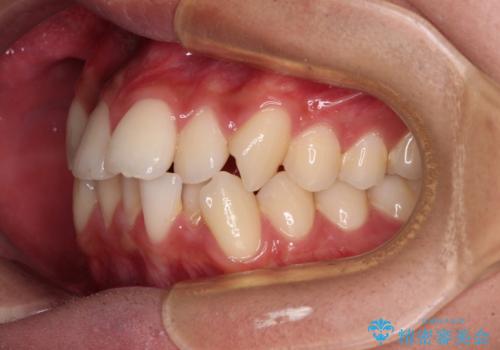

患者様の望んでいた通りの歯列や口元に仕上げることができました。